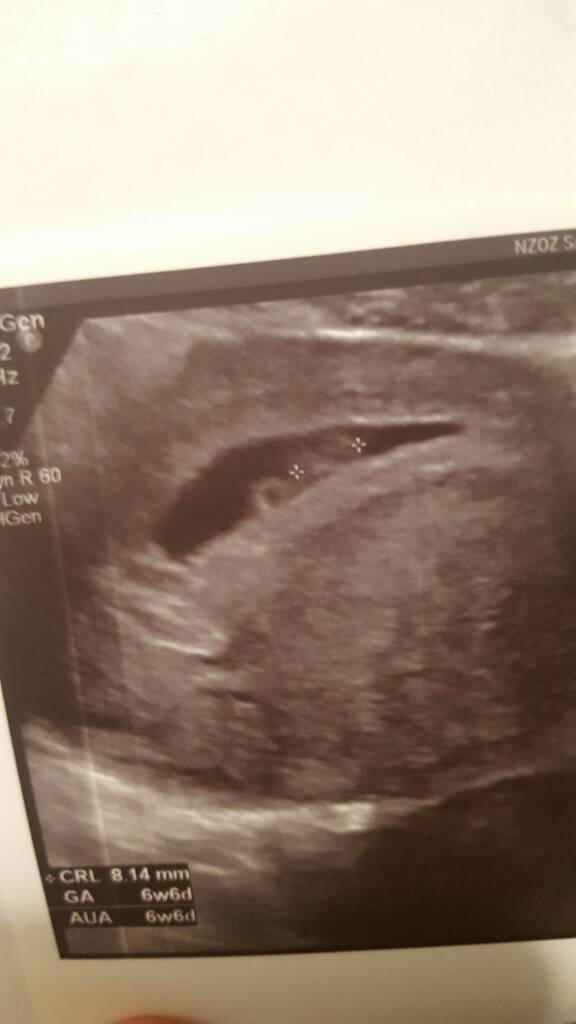

Gratulacje!!Dziewczyny ja tylko na chwilkę się przywitać i przedstawić nasza fasolę4 dni mlodsza ale za to serce bije jak dzwoń [emoji7] zdjęcie nie wyraźne bo robione przez brzuch (?) Ale jest!